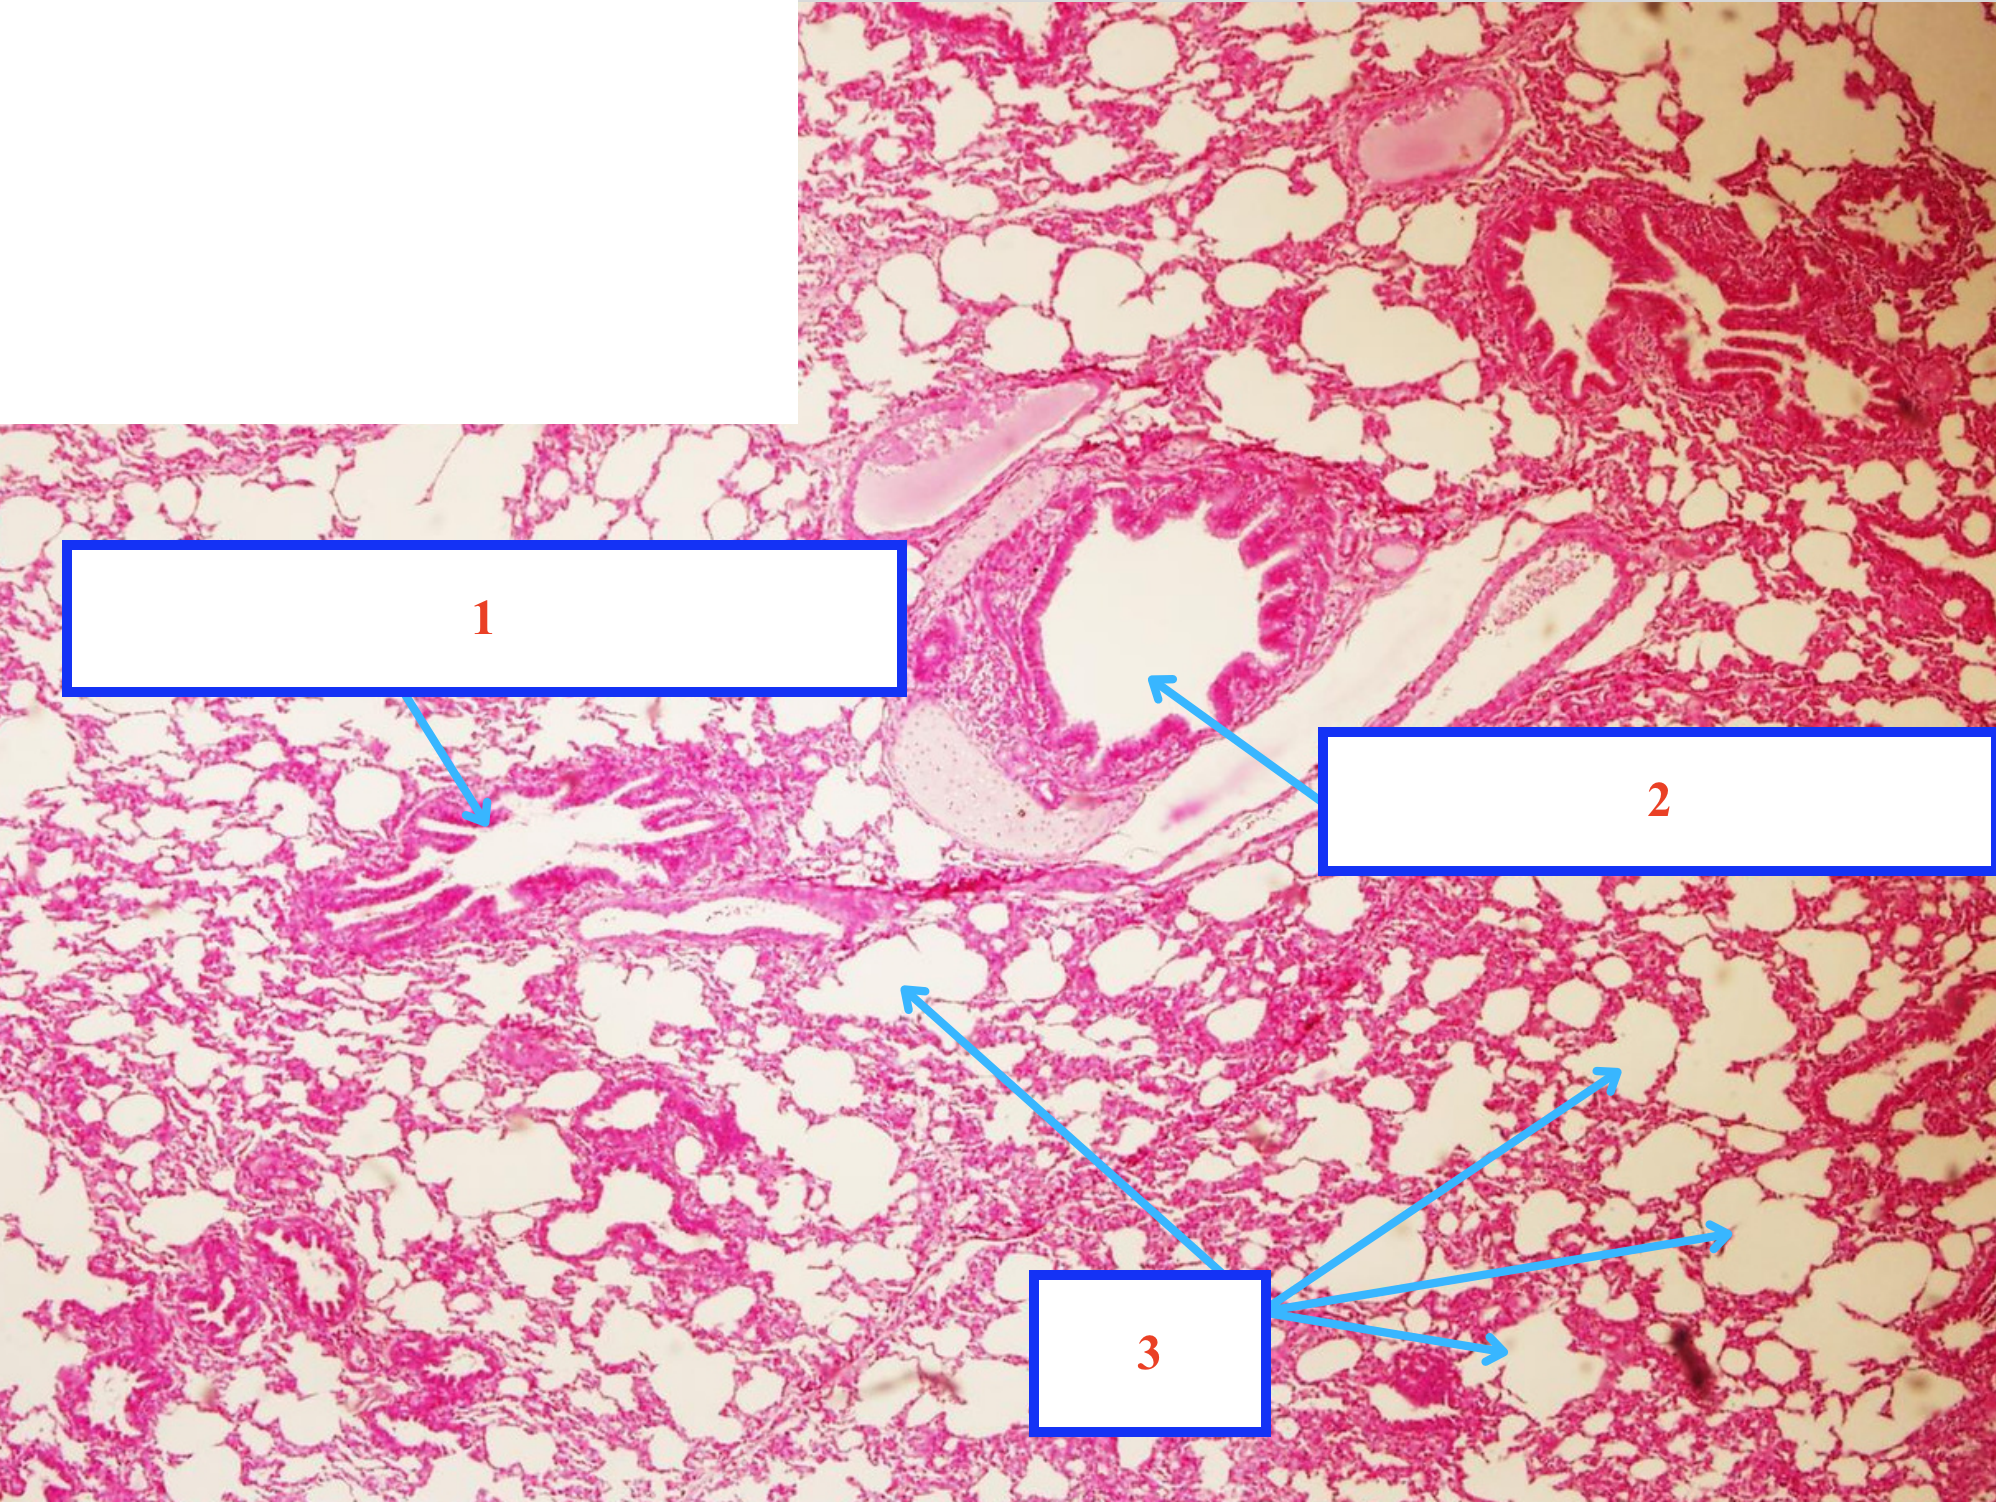

Cấu trúc gì ?

Tiểu phế quản chính thức

Phế quản gian tiểu thuỳ

Phế nang

Mạch máu